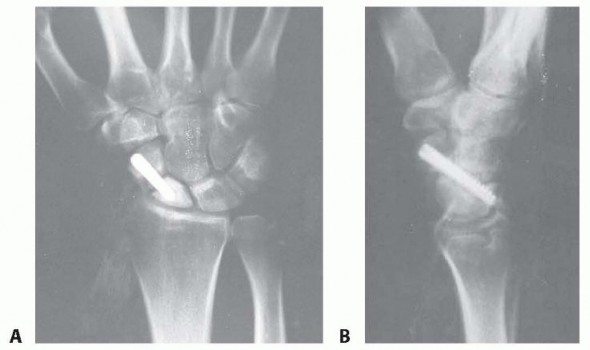

Reduction and Stabilization of the Distal Radioulnar Joint following Galeazzi Fractures